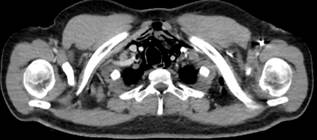

La radiografía de tórax no fue concluyente, por lo que se solicitaron una tomografía de cuello con contraste, que reportó la presencia de aire en el espacio perivertebral, carotídeo, visceral, retrofaríngeo con extensión al tórax y cervical posterior (Figura 2), y una tomografía de tórax con contraste que confirmó el diagnóstico de neumomediastino por la presencia de imagen hipodensa en el rango de aire, el cual provenía del cuello y se continuaba por el espacio visceral y prevertebral, además de comprometer el mediastino (Figura 3). Se realizó una junta médica en la que se decidió realizar una nueva EVDA para intentar la colocación de prótesis metálica autoexpandible totalmente recubierta con el fin de evitar una mediastinitis.

Imagen cortesía Dr. Edgardo Sánchez Gamboa.

Figura 2 Tomografía de cuello con contraste con presencia de aire en el espacio perivertebral, asociado a edema adyacente.

Figura 3 Tomografía de tórax con contraste con neumomediastino por presencia de imagen hipodensa en el rango de aire en el espacio visceral y prevertebral.